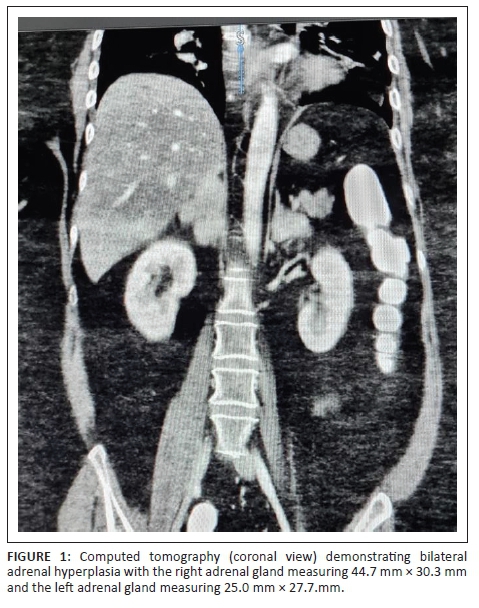

Abdominal contrasted computed tomography (CT) scan showed bilateral lobulated adrenal masses, with the right being larger than the left (right: 44.7 mm × 30.3mm, left: 25.0 mm × 27.7mm) (Figures 1 and 2), containing fat and soft tissue with no calcifications. Absolute washout of radiocontrast after 10 min was 65% bilaterally and the masses measured nine Hounsfield units (HU). Computed tomography Brain showed a normal pituitary gland. Dual-energy X-ray absorptiometry (DXA) scan demonstrated osteoporosis of the left femoral neck (T-score - 3.0).